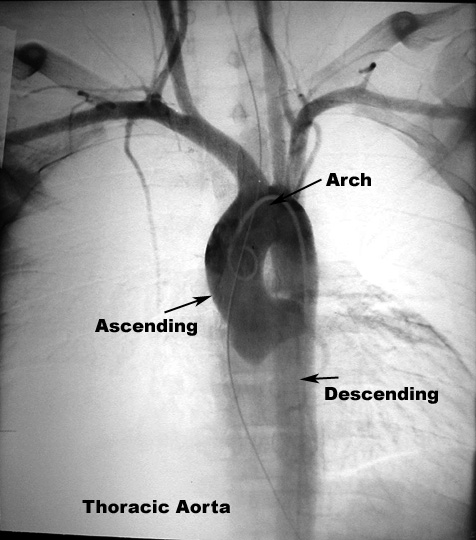

- the ascending aorta

- the arch of the aorta

- the descending aorta.